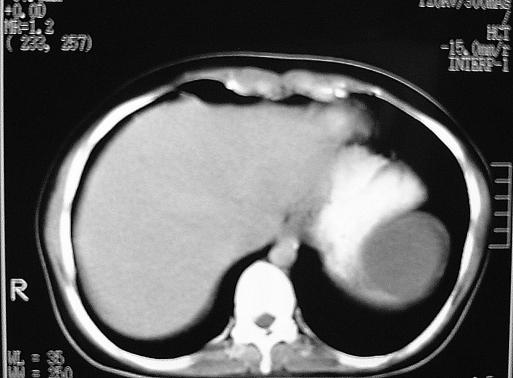

True nonparasitic splenic cysts are rare. Reports of approximately 30 cases of benign true splenic cysts producing elevated CA 19-9 serum levels have been published. The traditional treatment of splenic epidermoid cysts is splenectomy. However, with all the advances in laparoscopic surgery, conservative laparoscopic approaches are accepted as the most preferred techniques for this benign disease. Laparoscopic cystectomy with its minimal invasiveness and low morbidity is the ideal technique for properly selected patients. So far, only one case report of laparoscopic cystectomy for splenic epidermoid cyst with elevated CA 19-9 levels has been published. This is the second known report of this procedure being performed to remove a splenic epidermoid cyst in a patient with elevated CA 19-9 levels.

真性非寄生虫性脾囊肿较为罕见。已发表了约30例良性真性脾囊肿导致血清CA 19-9水平升高的报告。脾表皮样囊肿的传统治疗方法是脾切除术。然而,随着腹腔镜手术的所有进展,保守的腹腔镜手术方法被认为是治疗这种良性疾病的最优选技术。具有微创性和低发病率的腹腔镜囊肿切除术是为适当选择的患者的理想技术。到目前为止,仅发表了一例腹腔镜囊肿切除术治疗CA 19-9水平升高的脾表皮样囊肿的病例报告。这是该手术用于切除CA 19-9水平升高患者的脾表皮样囊肿的第二例已知报告。